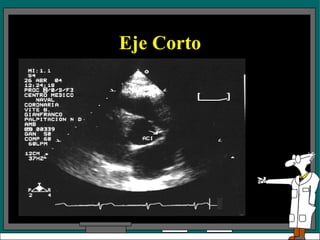

Eje corto Está aproximadamente a 90 grados del examen en el eje largo aórtico.

Eje corto Hay 4 posiciones del transductor para los exámenes en eje corto del VI. El plano l da una vista de la punta del corazón La posición 2 es una vista a nivel de los músculos papilares. El plano 3  esta a nivel de la válvula mitral. El plano cuatro da una vista a nivel de la válvula aórtica.

Eje Corto El espacio intercostal es el mismo para los planos 2, 3 y 4. El examen en el plano 1 requiere mover el transductor a un espacio intercostal inferior